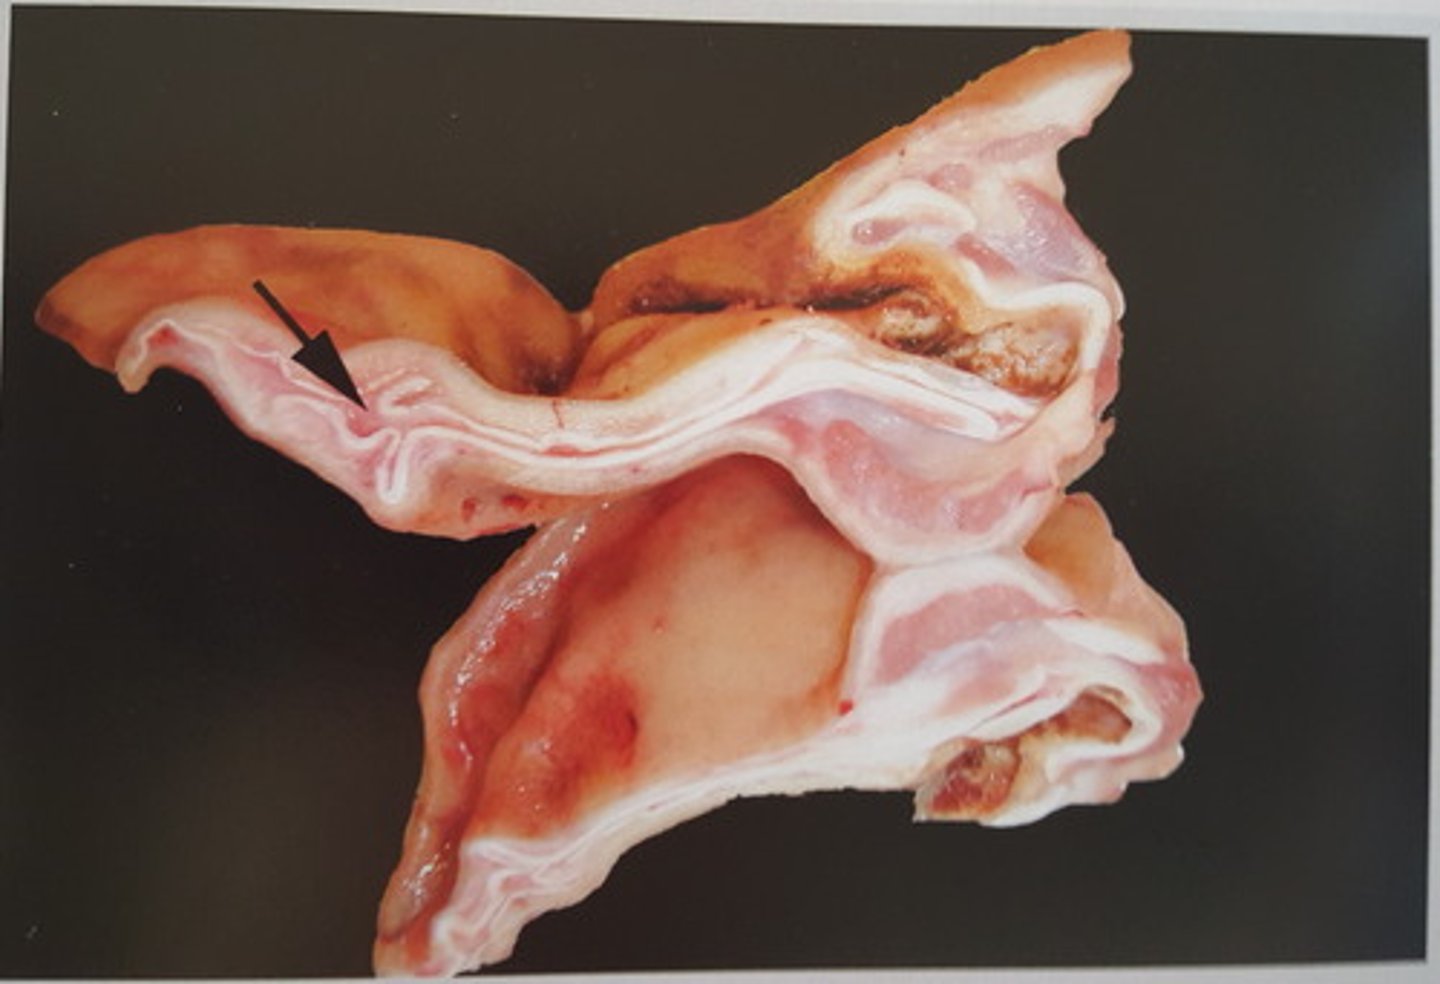

Lever fra okse, hvad er den patoanatomiske diagnose og hvorfor opstår det?

Lokal tensions steatosis

Her ses at hepatocytkernerne ligger perifært, hvilket skyldes at lipidet (triglyceridet) presser kernerne ud

/der kan også ses lokal hepatisk steatose (modsat diffus), ses ofte hvor der hænger ligamenter fast, hvor der typisk ses tensions steatoser, fordi når dyret går rundt, vil det hive i leveren, hvilket minimere blodforsyningen til det lokale område => hypoxi => transport af fedt nedsættes => lokal hepatisk steatose